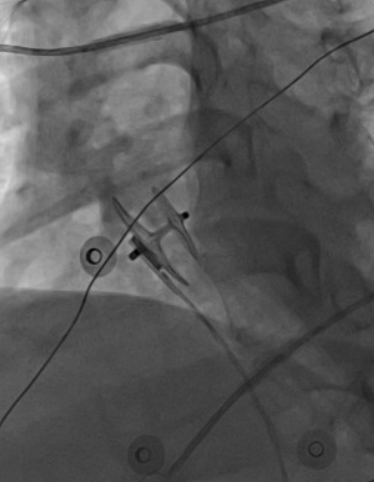

近日,沧州市中心医院心血管内五科为一名卵圆孔未闭(PFO)合并有脊柱侧弯和后突畸形的患者成功进行了卵圆孔未闭介入封堵术,这是沧州市首例心腔内超声(ICE)引导下完成的PFO封堵术。

该患者有多年的头痛病史,经神经内科筛查考虑为PFO,并经过规范药物治疗,效果不明显,来PFO专病门诊找到医院心血管内五科副主任牛和平,经过仔细询问病史,查看相关检查结果,诊断PFO明确,考虑患者有介入封堵的指征,而后收入院。但患者患有先天脊柱侧弯及后突,血管及心脏结构有明显转位,常规超声并不能完全准确引导介入操作,为介入手术带来极大的困难和风险。医院副院长、心血管内五科主任张军教授,副主任牛和平,副主任付金国,副主任医师王磊,主治医师于恺等反复讨论,决定实施ICE指导下PFO介入封堵术。术中,在ICE的实时引导下,传送鞘管顺利进入右心房,明确PFO的位置后导丝成功通过未闭卵圆孔进入左房,之后顺利植入封堵器,ICE实时确认封堵术释放位置良好,封堵效果极佳,手术时间不到半小时,患者恢复良好,目前已经出院。

与常规经胸超声相比,ICE 具有更高的图像分辨率,依靠其探头的灵活性,可从多个切面对房间隔成像,有助于精确测量卵圆窝的直径、房间隔的长度、PFO隧道长或宽、 隧道入口及出口直径;同时可以观察 PFO 患者心 房水平的分流情况,明确有无过长的 Eustachian 瓣 或Chiari网、ASA、双层隔等特殊的复杂结构。介入封堵术中,ICE 能实时监测并指导手术过程,帮助术者精准确定 PFO 的位置,全程直视下释放封堵器,评 价封堵器的形状、位置和稳定性。同时,可通过注 射生理盐水和(或)彩色多普勒检查来确认有无残 余分流。在 TTE 声窗差、不耐受 TEE、解剖特征复 杂型 PFO、PFO 封堵术后残余漏二次介入的患者 中,ICE引导或辅助下进行 PFO封堵术能明显提高手术成功率。ICE的另一优势是可减少术中X线暴 露时间,有效降低对患者(特别是肥胖者)和术者的 辐射危害。